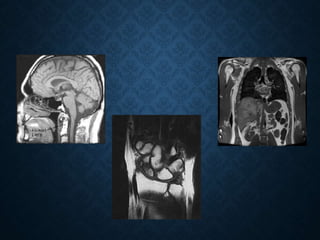

• O diagnóstico de patologias através da RMN pode ser realizado

através de comparações entre o sinal produzido no tecido normal

e o sinal produzido no tecido alterado.

APLICAÇÕES CLÍNICAS • Odiagnóstico de patologias através da RMN pode ser realizado através de comparações entre o sinal produzido no tecido normal e o sinal produzido no tecido alterado.